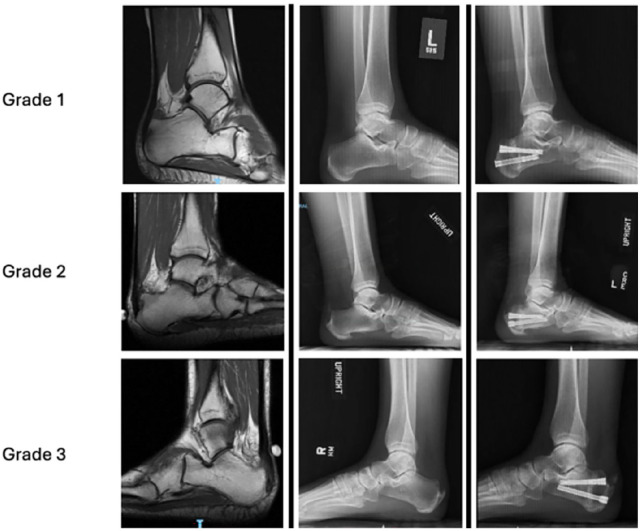

Methods: Patients who underwent MIS ZO for IAT ± Haglund deformity were identified and retrospectively analyzed. IAT severity was graded on preoperative MRI. Patient Reported Outcome Measurement Information System (PROMIS) scores, complications, and revisions were recorded. Continuous data were compared by analysis of variance with Bonferroni post hoc analysis.

Results: Seventeen patients treated with MIS ZO, with follow-up >6 months, and preoperative MRI met our inclusion criteria. PROMIS pain scores significantly improved in patients with IAT grades 1-3, with 5, 5, and 7 patients, respectively, in each subgroup. In this small series we only identified statistically significant improvements in PROMIS function (P = .031), and mobility (P = .009) scores were only observed in patients with grade 2 pathology. Sixteen of 17 patients (94.2%) were very satisfied with their procedure and would undergo it again.